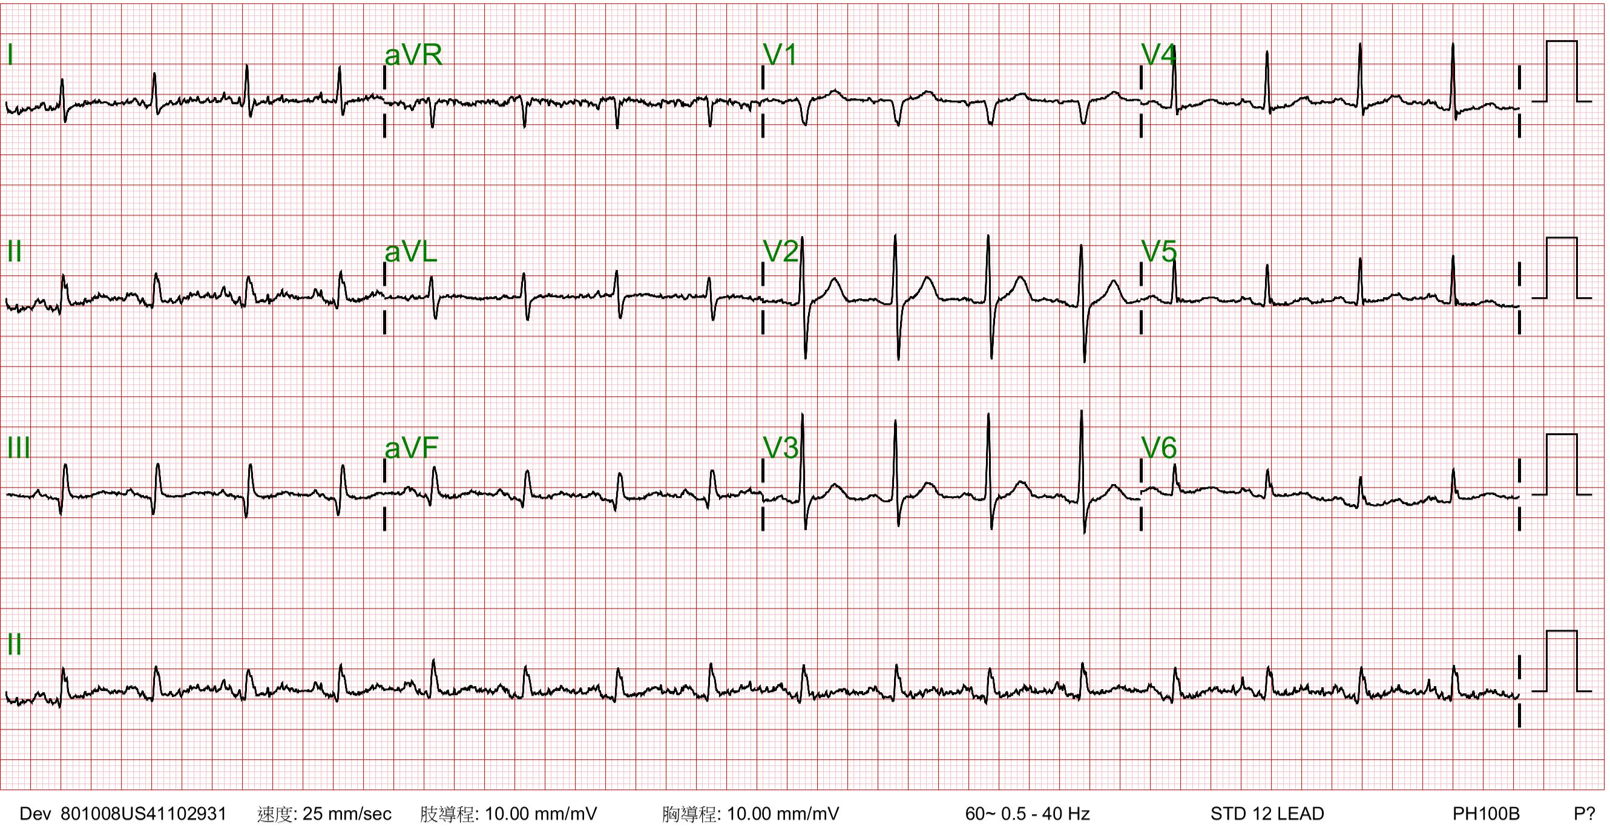

Echocardiography showed normal ejection fraction. His ECG showed Sinus rhythm and Q wave in inferior leads.